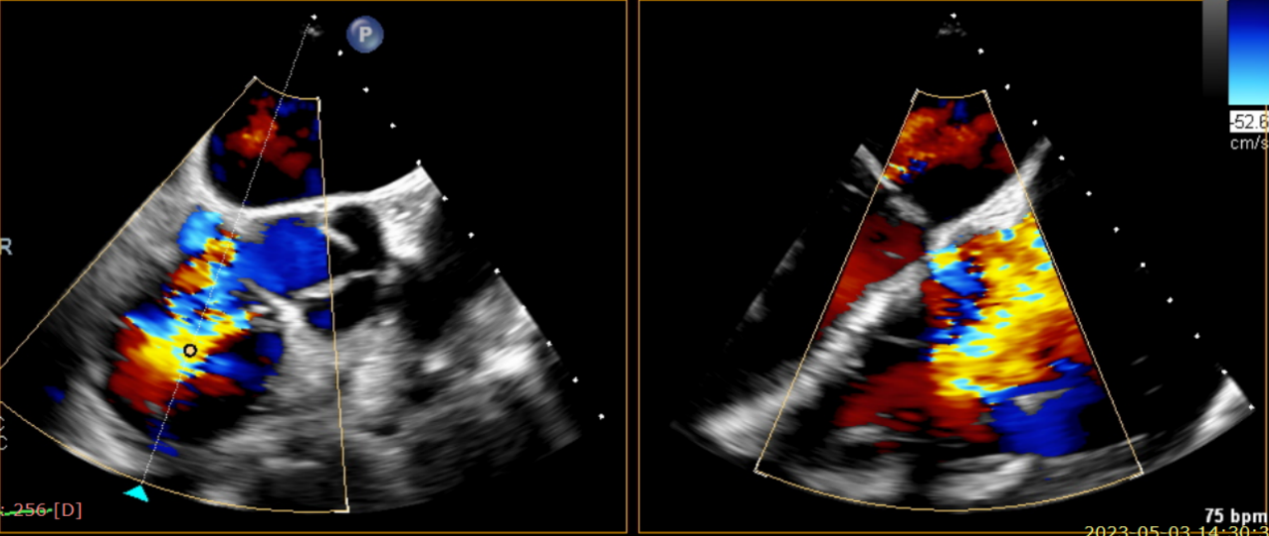

術(shù)前超聲提示大量三尖瓣反流